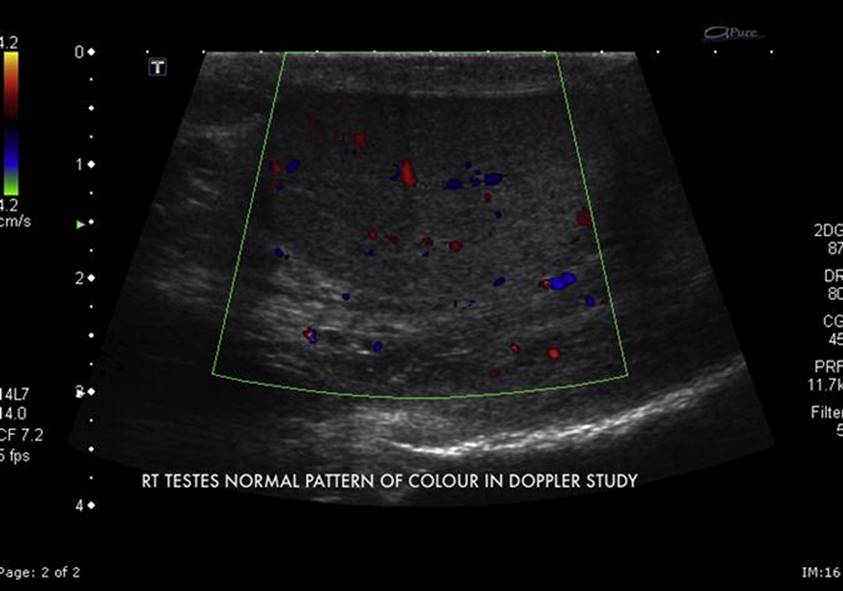

Colour Doppler imaging of the testis

It is useful in diagnosing torsion but also in elucidating other scrotal pathology. Comparison of blood flow to the asymptomatic side is crucial. If there is reduced flow to one side then some degree of torsion must be suspected (E-Fig. 10.2.1 and E-Fig. 10.2.2). If the testis has untwisted, hyperaemic flow may be noted. The sensitivity of colour Doppler imaging (CDI) for torsion can be as low as 82%, missing one in five cases, and is affected by:

E-FIG. 10.2.1 Shows a normal colour flow pattern in the patients right testicle.